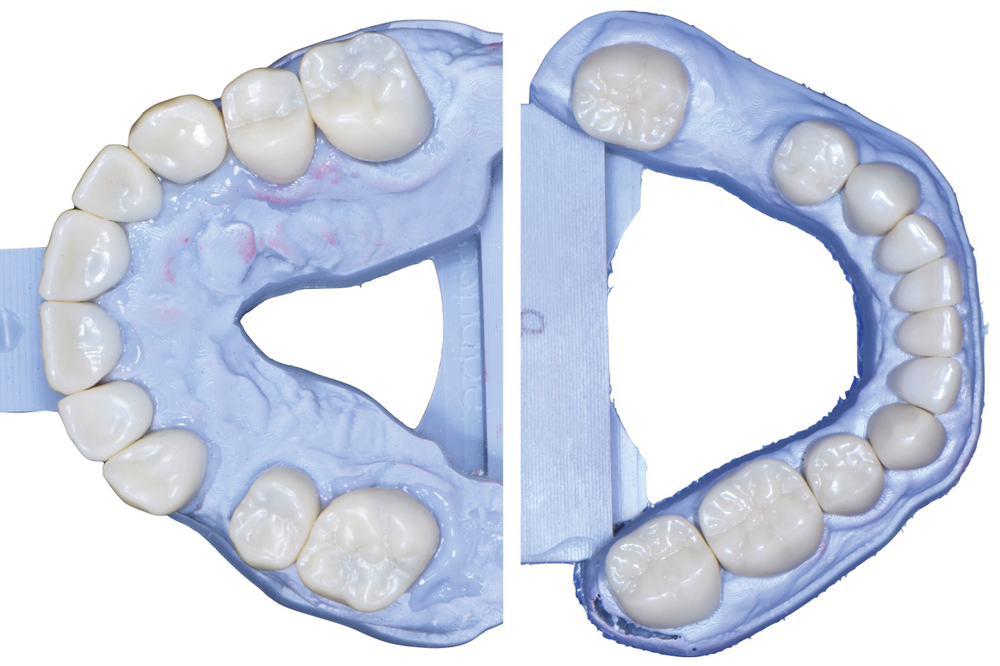

Au vu du contexte para-fonctionnel et de l’étendue de la perte tissulaire, des coiffes périphériques minimalement invasives ont été choisies afin de restaurer l’esthétique et la fonction. Actuellement, aucun consensus n’est fait sur le choix du matériau d’infrastructure à privilégier. Les matériaux hybrides usinables présentent des propriétés mécaniques, physiques et biologiques intéressantes en contexte d’usure sévère (e.g., module d’élasticité, résistance à la propagation de fêlures, facilité de réintervention). Une réhabilitation globale avec remontée de dimension verticale d’occlusion (DVO) par l’intermédiaire de coiffes composites renforcés en nano-céramiques est décrite.